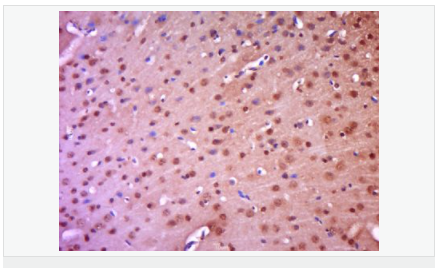

交叉反應(yīng):Human,Mouse,Rat(predicted:Pig,Cow,Rabbit,Sheep) 推薦應(yīng)用:WB,IHC-P,IHC-F,IF,Flow-Cyt,ELISA

| 產(chǎn)品應(yīng)用 | WB=1:500-2000 ELISA=1:5000-10000 IHC-P=1:100-500 IHC-F=1:100-500 Flow-Cyt=1μg/Test ICC=1:100 IF=1:100-500 (石蠟切片需做抗原修復(fù)) not yet tested in other applications. optimal dilutions/concentrations should be determined by the end user. |